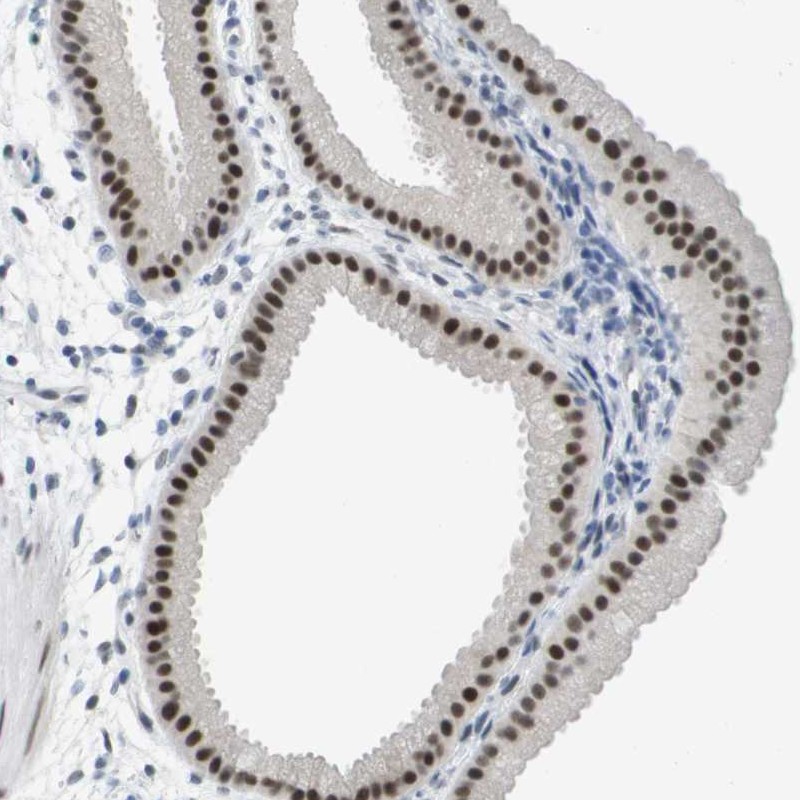

Immunohistochemical staining of human gallbladder shows strong nuclear positivity in glandular cells.